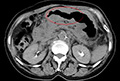

画像引用元:東京MITクリニックHP(http://www.comfort-hp.com/pages/03.html) 手術を拒否した50代―【食事ができない状況から一転】手術をすすめられたが拒否。食事療法やサプリメントで撃退したいと考えたが、体力・体重の減少。食事も取れなかったが、免疫療法12ヶ月で塞がっていた胃が開通。